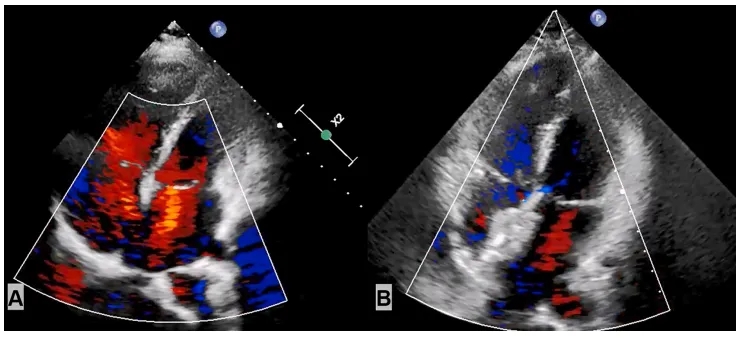

2025年2月4日:患者入院接受经皮ASD封堵术,右心导管检查示PAP 45/13(25)mmHg,Qp/Qs为2.5,PVR 3.5 WU。术中选用26mmASD封堵器成功完成封堵。术后PAP 40/10(22)mmHg,超声心动图示封堵器位置、大小、形状合适,未影响周边心脏结构(图3)。

图3:经皮ASD封堵术前后超声心动图

(A)术前超声心动图显示ASD,(B)封堵完成后超声心动图。